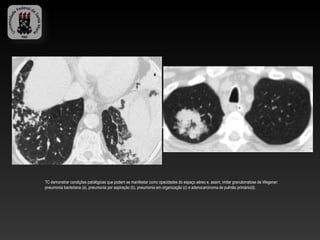

TC demonstrar condições patológicas que podem se manifestar como opacidades do espaço aéreo e, assim, imitar granulomatose de Wegener:

pneumonia bacteriana (a), pneumonia por aspiração (b), pneumonia em organização (c) e adenocarcinoma de pulmão primário(d).

TC demonstrar condiçõespatológicas que podem se manifestar como opacidades do espaço aéreo e, assim, imitar granulomatose de Wegener: pneumonia bacteriana (a), pneumonia por aspiração (b), pneumonia em organização (c) e adenocarcinoma de pulmão primário(d).